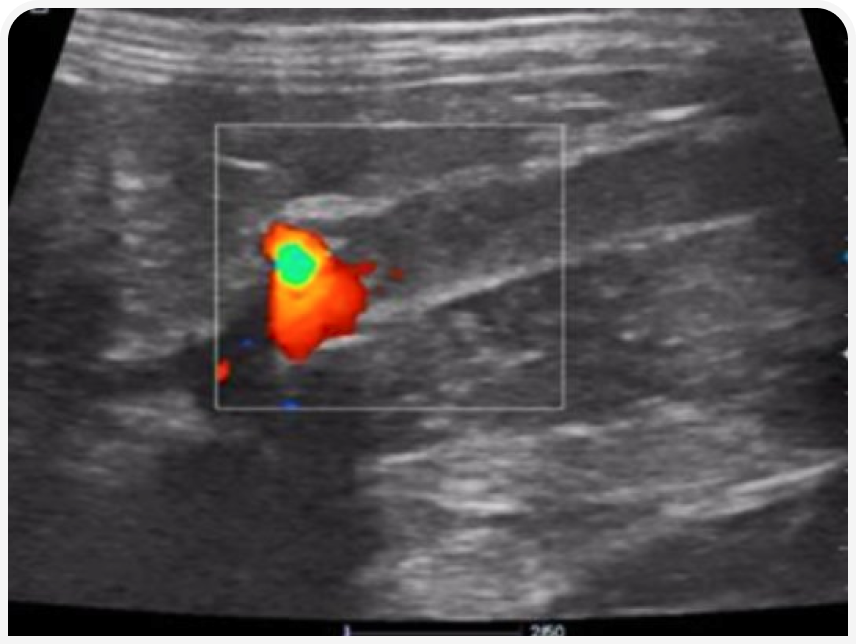

Диагноз подтверждается непроходимостью артерий на основании исчезновения сигналов при доплерографии или визуализацией тромбов в артериях с помощью ультразвукового сканирования.

УЗИ-скрининг брюшной полости для определения границ аортального поток. Аортальный кровоток можно визуализировать с помощью цветового доплера. Аорта визуализируется дорсальнее мочевого пузыря (рис. 6).